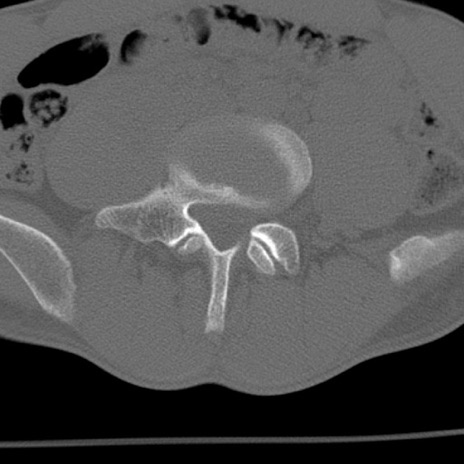

症例3 腰椎CT(横断像)

腰椎CT